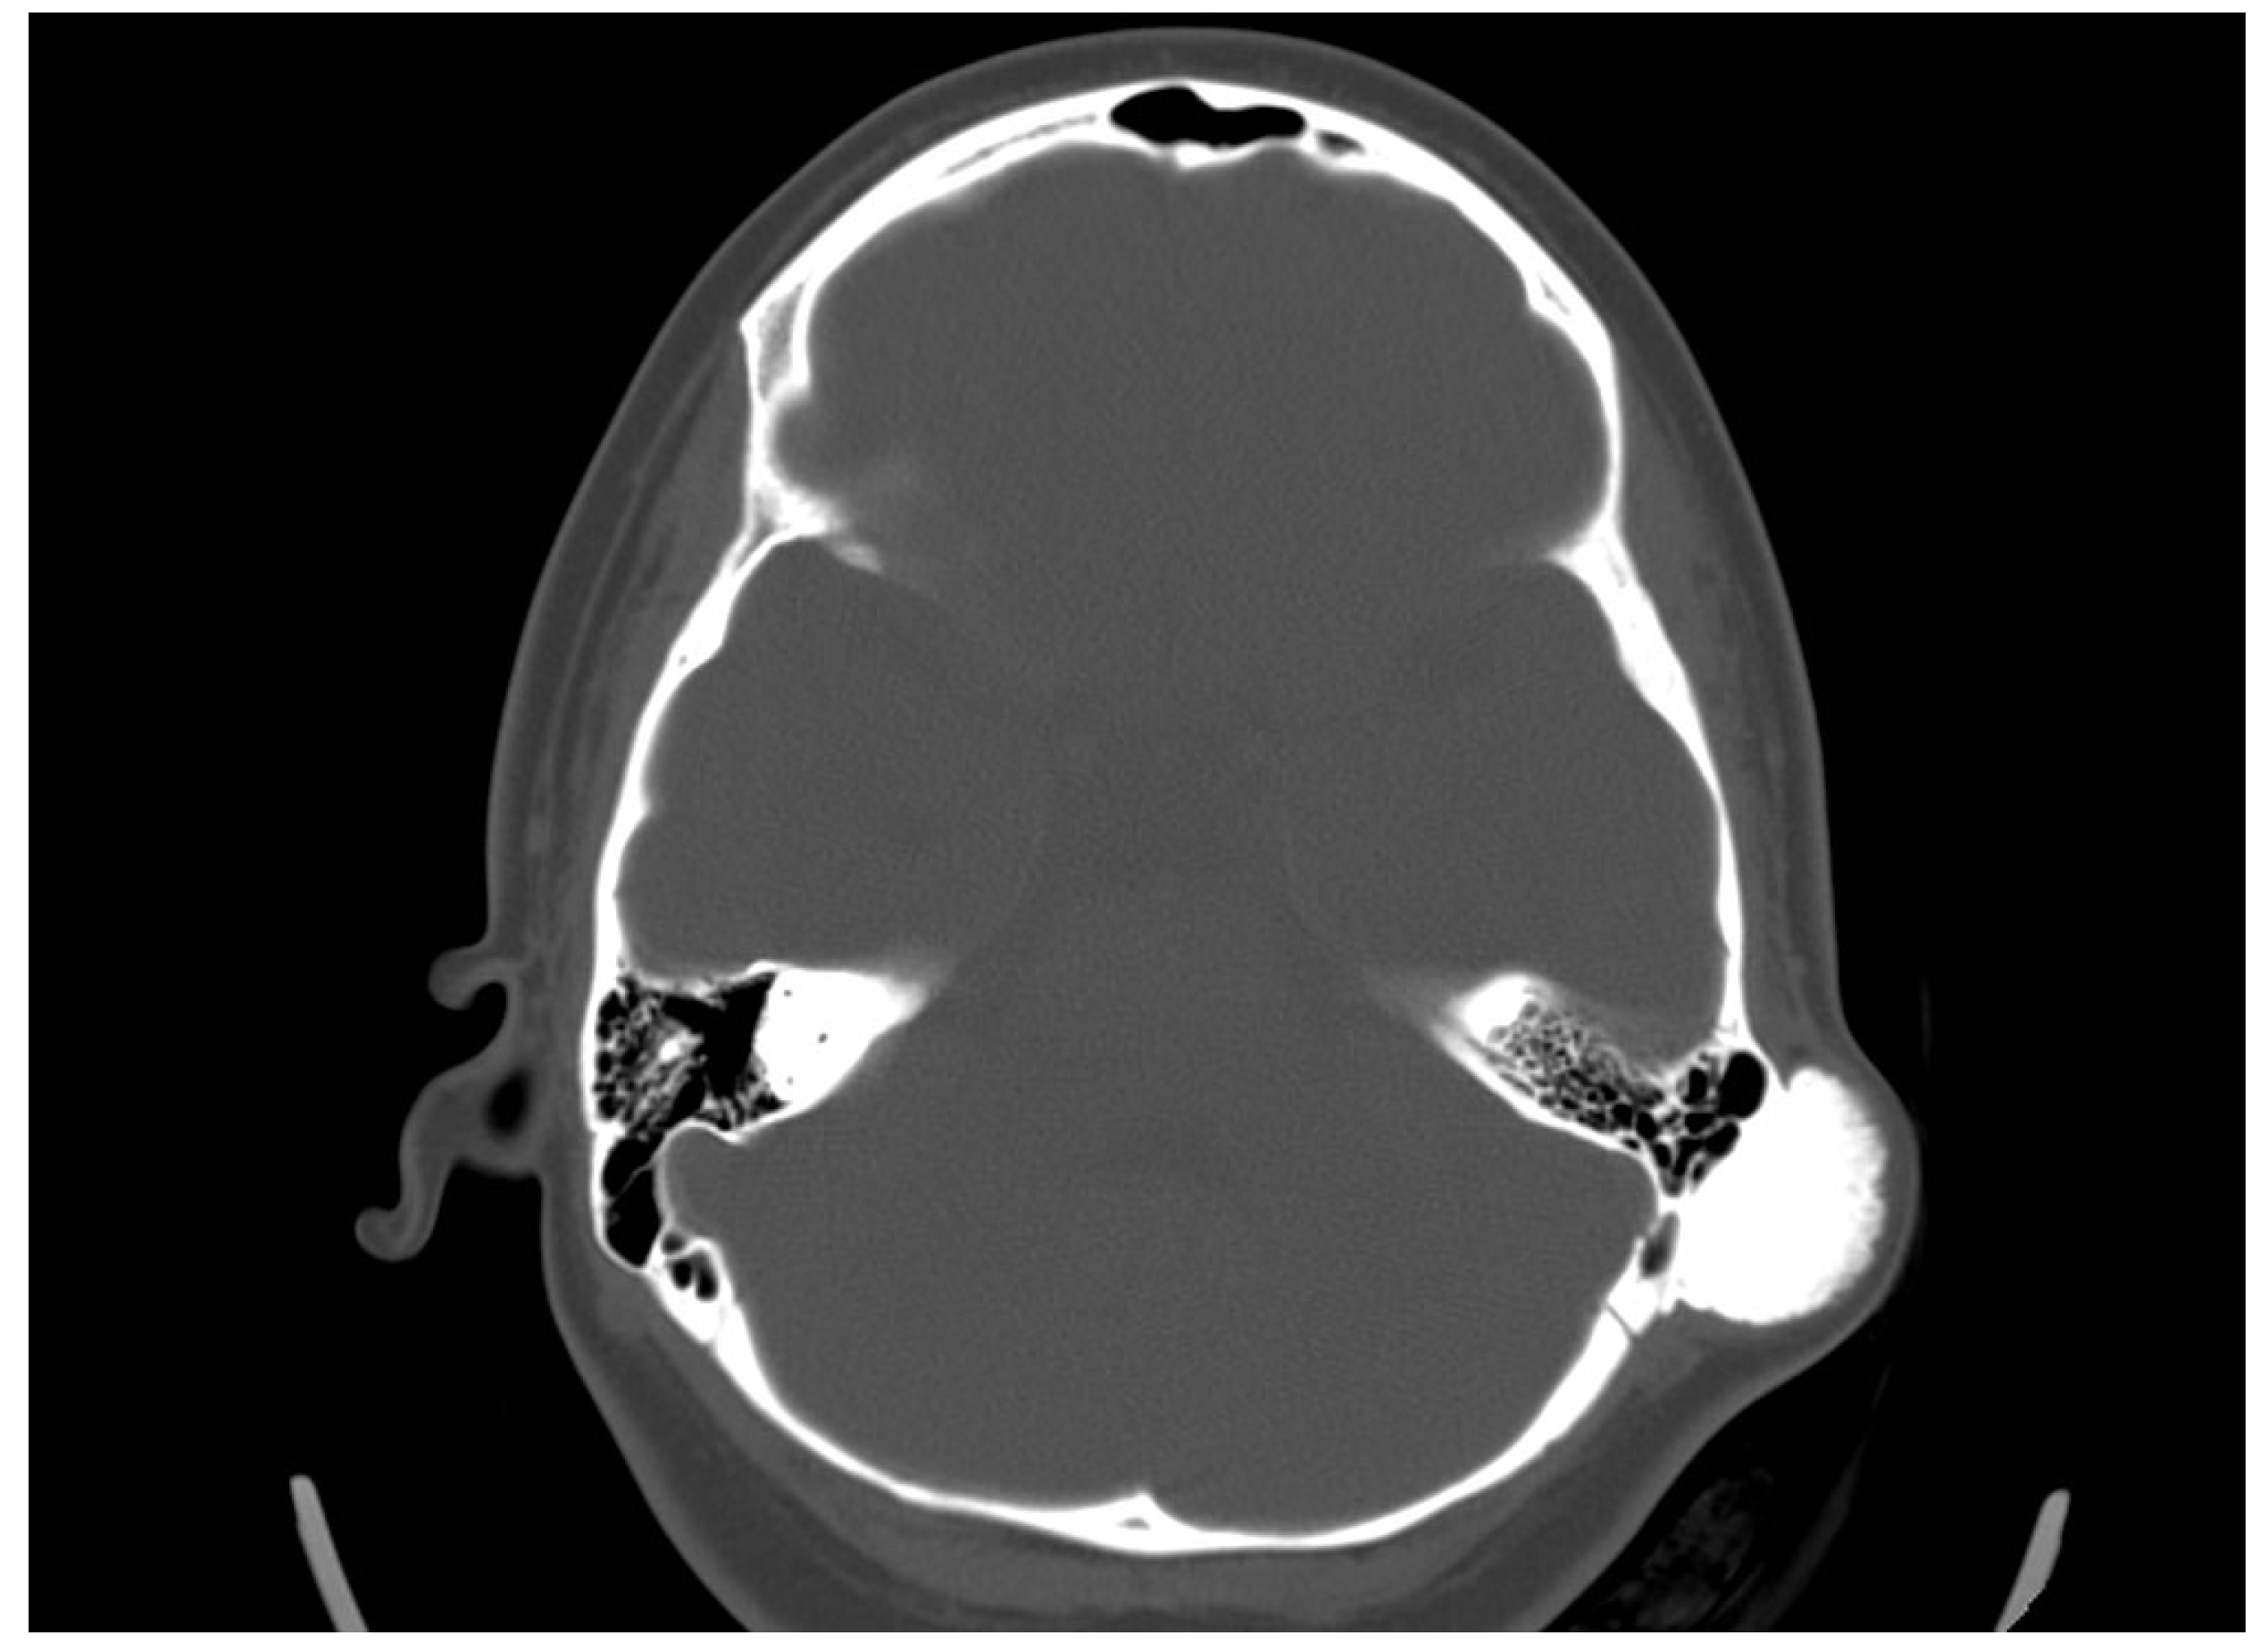

She was admitted to the ENT department, and an otorhinolaryngological examination was performed. In the retroauricular area, tumor formation was palpated, and the overlying skin was mobile with no retraction. Otoscopy did not detect any abnormalities in the external auditory canal and the tympanic membrane. The audiological examination did not indicate any hearing loss. A computed tomography scan was conducted. In the axial plane, a bone tumor formation with a diameter of 19/31 mm in the mastoid process was detected. There was a passive dislocation of the soft tissues with no invasion (Figure 3).

Figure 3. Axial CT scan revealing an osteoma in the cortex of the mastoid process, with no involvement of the surrounding cellular structures.